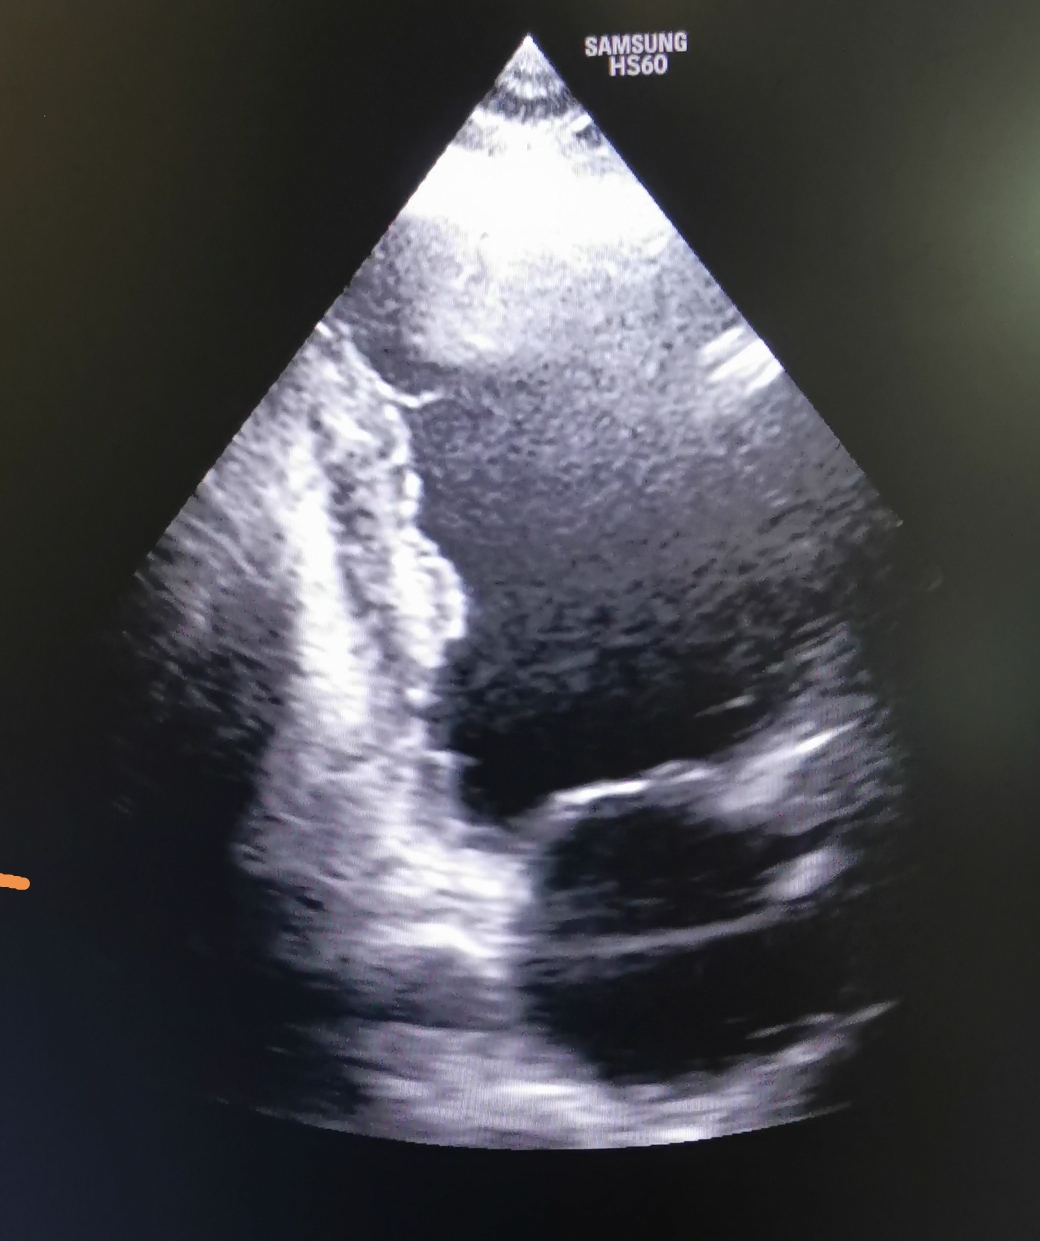

Trombul intracardiac

Tromb (cheag) cardiac, apărut prin perturbarea circulației intracardiace a sângelui, în acest caz prin contracție deficitara a muschiului cardiac cu scăderea forței de expulzare. Trombul din imagine este mai vechi de 12 luni, este organizat, riscul de fragmentare și embolizare este foarte mic în urma endotelizarii, iar funcția contractila a inimii este imbunatatita fata deContinuă lectura „Trombul intracardiac”